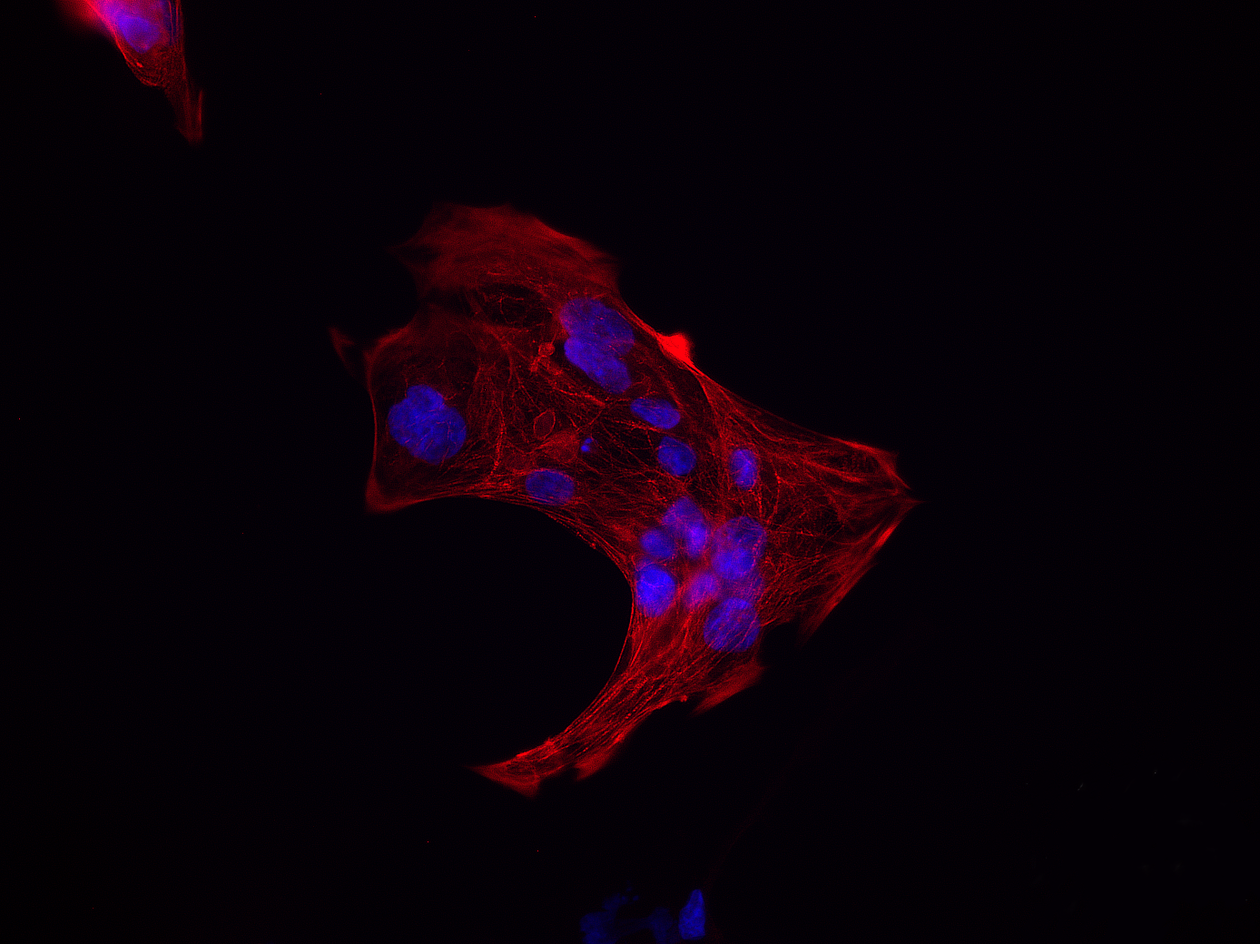

We are using stem-cells transformed from the patient’s own fibroblasts to study the mitochondrial disease caused by POLG mutations. These “induced pluripotent stem cells” (iPSC) offer a unique opportunity to model human disease in a renewable and tissue-specific manner. Thus far we have successfully generated neurones and all glial cell types, cardiomyocytes, and hepatocytes from these iPSCs.

We have established the required competence and facilities for human induced pluripotent stem cell (hiPSC) reprogramming and differentiation, enabling investigation of neuronal cells from patients and healthy controls. Validated iPSCs are differentiated to neural stem cells (NSCs) and regionalized neuronal subtypes, as well as astrocytes/ glial populations. A postdoctoral fellow in our group, Yu Hong, has developed brain organoids and will be using these both to investigate disease mechanisms and to test treatments.

- 2D: neural stem cells, DA neurons, motor neurons, generic neurons, astrocytes, oligodendrocytes and cardiomyocytes.

- Co-culture systems

Modeling diseases using neural stem cells, neurons, astrocytes, and astrocyte-neurons interactions.